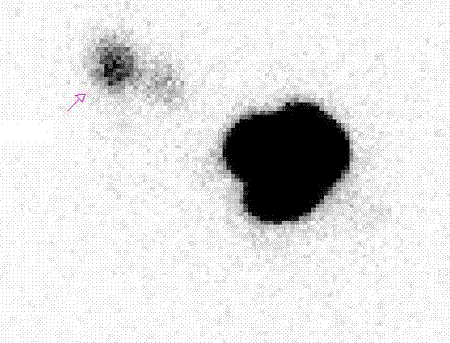

“Việc phẫu thuật nạo vét hạch nách cộng với việc phải tia xạ để phòng di căn khiến đường dẫn lưu bạch huyết từ cánh tay về tuần hoàn chung bị ảnh hưởng, gây tình trạng bạch huyết ở tay dần dần ứ trệ, gây hiện tượng phù “tay voi”, khiến tay người phụ nữ sau phẫu thuật to lên rất nhiều, có những người kích thước tay còn to hơn đùi”, TS Quang cho biết.

Đáng nói, tỉ lệ bị phù “tay voi” khá cao. Thống kê tại Bệnh viện K cho thấy, có từ 15-30% chị em sau phẫu thuật ung thư vú bị biến chứng phù “tay voi”. Tùy từng trường hợp mà biến chứng phù “tay voi” xuất hiện sớm hay muộn. Có người sau mổ là có biểu hiện ngay, nhưng cũng có những trường hợp xuất hiện muộn. Đáng nói, phù “tay voi” không chỉ ảnh hưởng đến thẩm mỹ, mà có những trường hợp “tay voi” diễn tiến xấu, bệnh nhân buộc phải tháo khớp, ảnh hưởng rất nhiều đến cuộc sống.